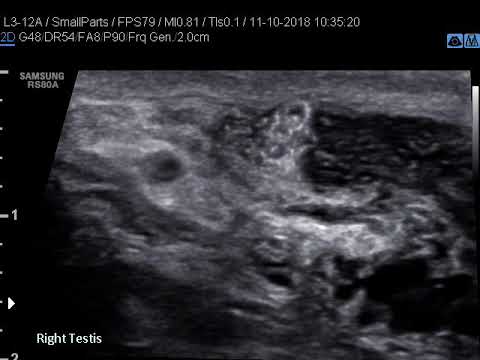

Dance Of Live Adult Filarial Worms Is A Reliable Sign Of Scrotal Filarial Infection Chaubal 2003 Journal Of Ultrasound In Medicine Wiley Online Library

Figure 2 From The Filarial Dance Sign In Scrotal Filarial Infection Semantic Scholar

Scrotal Filariasis The Importance Of Filarial Dance Sign In Scrotal Ultrasound

Scrotal Ultrasound Shows The Characteristic Filarial Grepmed